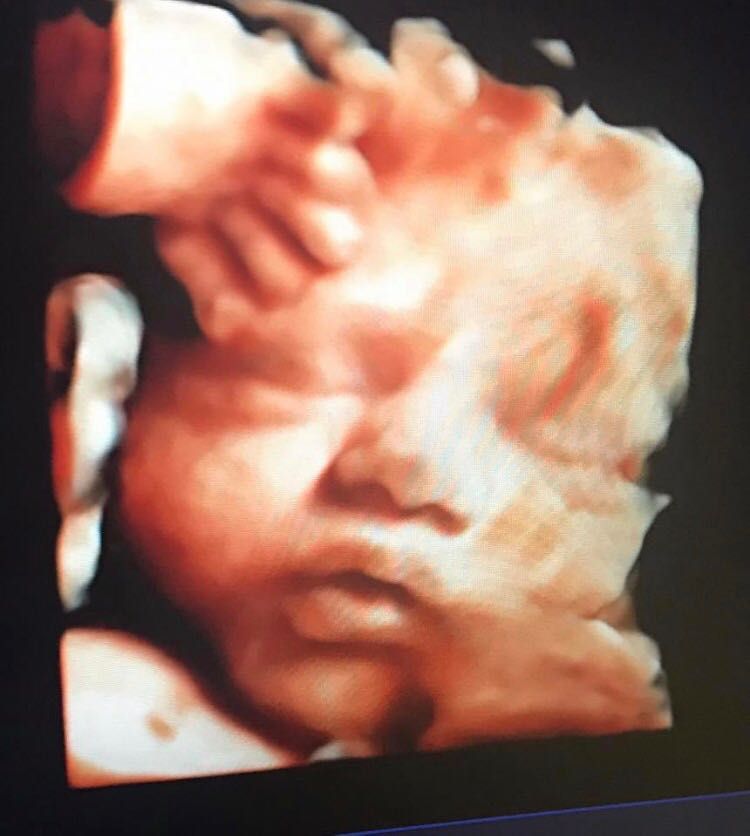

Mi sono sempre dedicata all’ecografia sia ostetrica che ginecologica. Seguo da sempre con dedizione le gravidanze, occupandomi anche dell’aspetto ecografico, come translucenza nucale, morfologica, eco 3D e 4D

Ecografia 3D

120 € -

Ecografia 4D

Consigliatissima!• Studio privato • ecografia 3D •